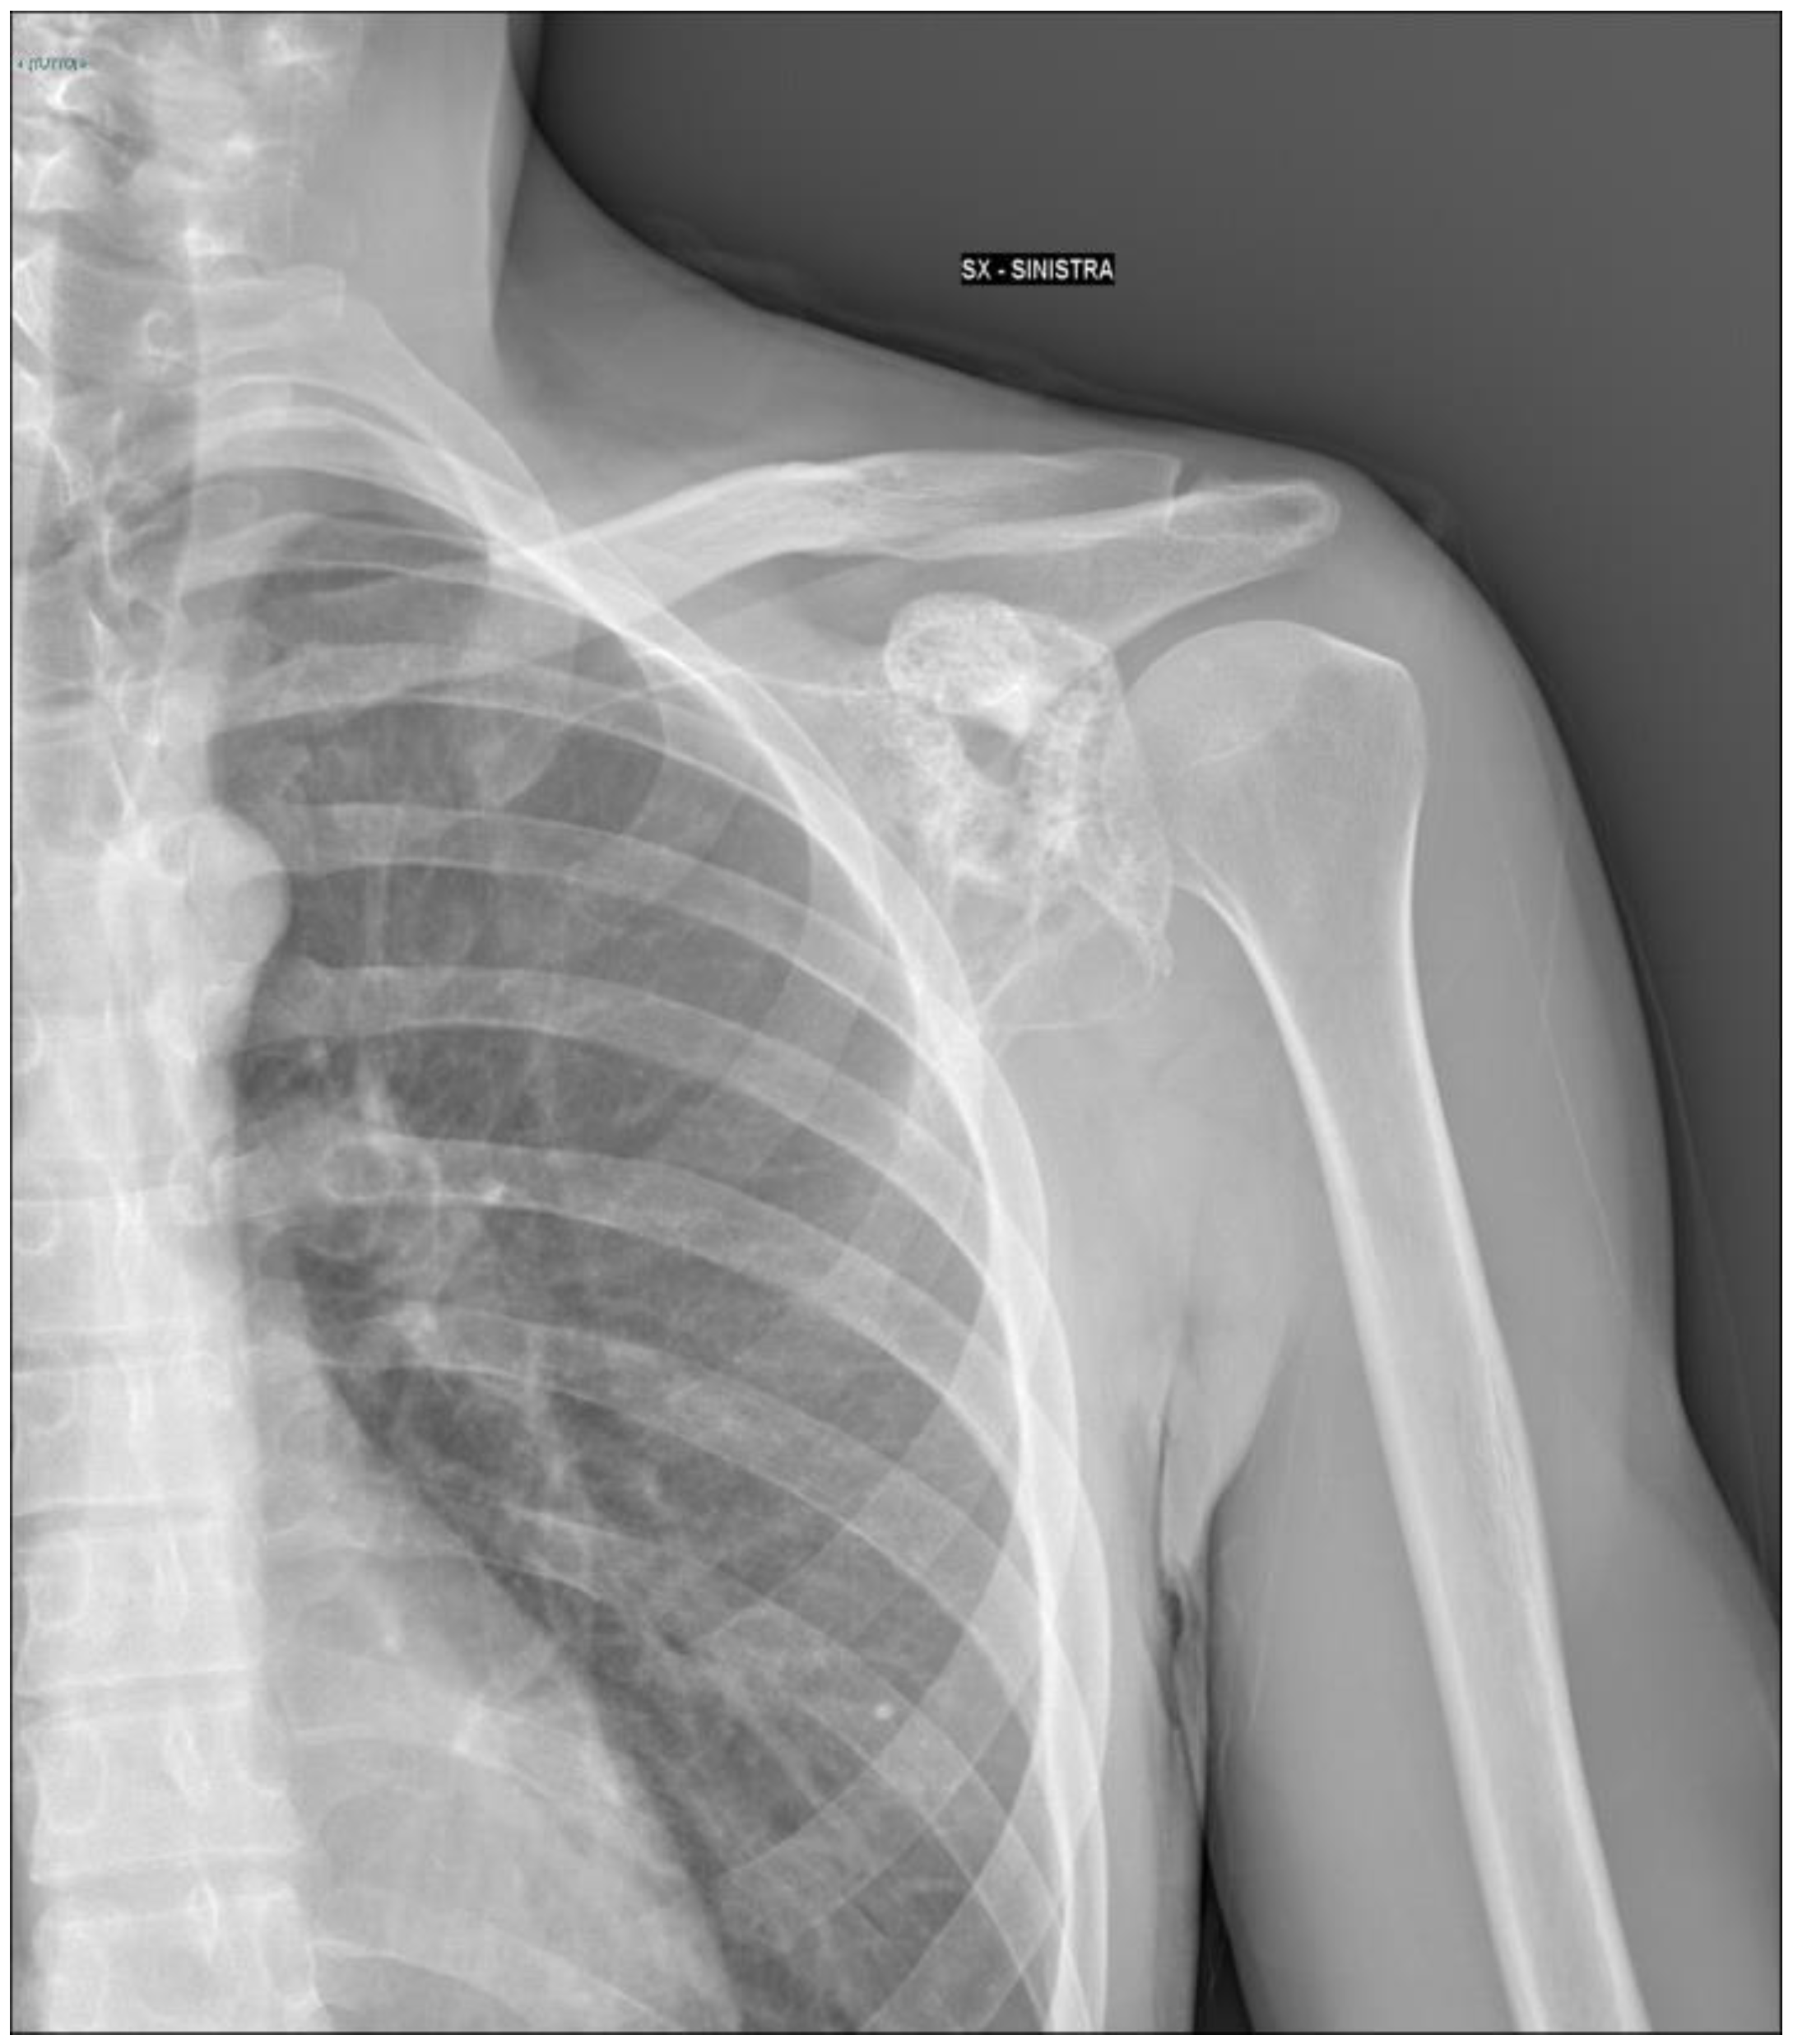

2.1. Oncological Staging